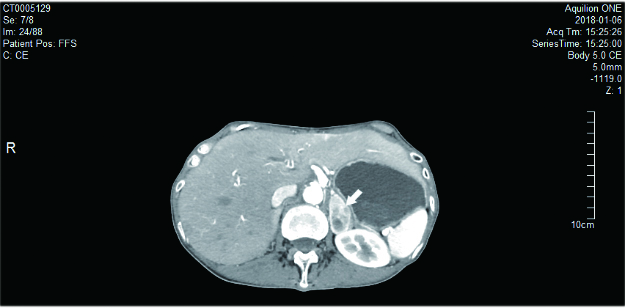

患者1,女,22岁,因“发现肾上腺占位10 d”入住我院泌尿外科,无头痛、心悸、大汗,无高血压、低血钾,无满月脸、水牛背、皮肤紫纹,无月经紊乱等不适。完善皮质醇节律及醛固酮肾素比值后未见明显异常,尿香草扁桃酸(vanillylmandelic acid, VMA):26.20(0.1-68.6)μmol/24 h。肾上腺增强MRI:右侧肾上腺区域见类圆形等T1长T2异常信号影,大小约29 mm×37 mm,嗜铬细胞瘤可能性大(图 1A)。增强CT:右侧肾上腺见肿块影,大小约38 mm×29 mm,嗜铬细胞瘤可能(图 1B)。全麻下行腹腔镜下右肾上腺肿瘤切除术,手术过程顺利,术中血压心率平稳。手术病理:(右肾上腺)嗜铬细胞瘤。术后患者无明显不适,血压平稳,出院后未予特殊治疗。术后20天患者出现头痛,伴头晕、恶心呕吐,四肢抽搐2次,抽搐时伴双眼上视,至我院急诊就诊。查体:体温37.7℃,脉搏140次/min,血压205/148 mmHg,心律齐,双下肢无水种。辅助检查:血甲氧基去甲肾上腺素:111.3(< 112) pg/mL,血甲氧基肾上腺素:54.8 (< 61)pg/mL,尿VMA:56.20(0.1-68.6)μmol/24 h。心电图:窦性心动过速,下壁异常Q波伴ST段抬高改变,前侧壁、高侧壁ST段压低。头颅MRI:两侧枕顶叶及部分额叶皮质、左侧尾状核头肿胀伴信号异常,考虑可复性后部性脑白质病综合征可能。间碘苄胍(metaiodobenzylguanidine, MIBG)显像:肾上腺髓质显像未见明显异常。入院后予乌拉地尔、硝酸甘油静脉维持控制血压,血压稳定后逐渐减量,加用多沙唑嗪、厄贝沙坦。1周后患者症状缓解,血压平稳,复查头颅MRI未见明显异常。出院后继续口服多沙唑嗪、厄贝沙坦治疗。半年后逐渐停药,血压监测平稳。

图 1 肾上腺增强MRI:右侧肾上腺区域见类圆形等T1长T2异常信号影,大小约29 mm×37 mm,内部信号欠均匀,边缘光整,下腔静脉受压前移,增强后病灶明显持续性强化,嗜铬细胞瘤可能性大(箭头)。

B:肾上腺增强CT:右侧肾上腺见肿块影,大小约38 mm×29mm,内部密度不均,增强扫描呈明显不均匀强化,边界尚清,下腔静脉受压前移,嗜铬细胞瘤可能(箭头)